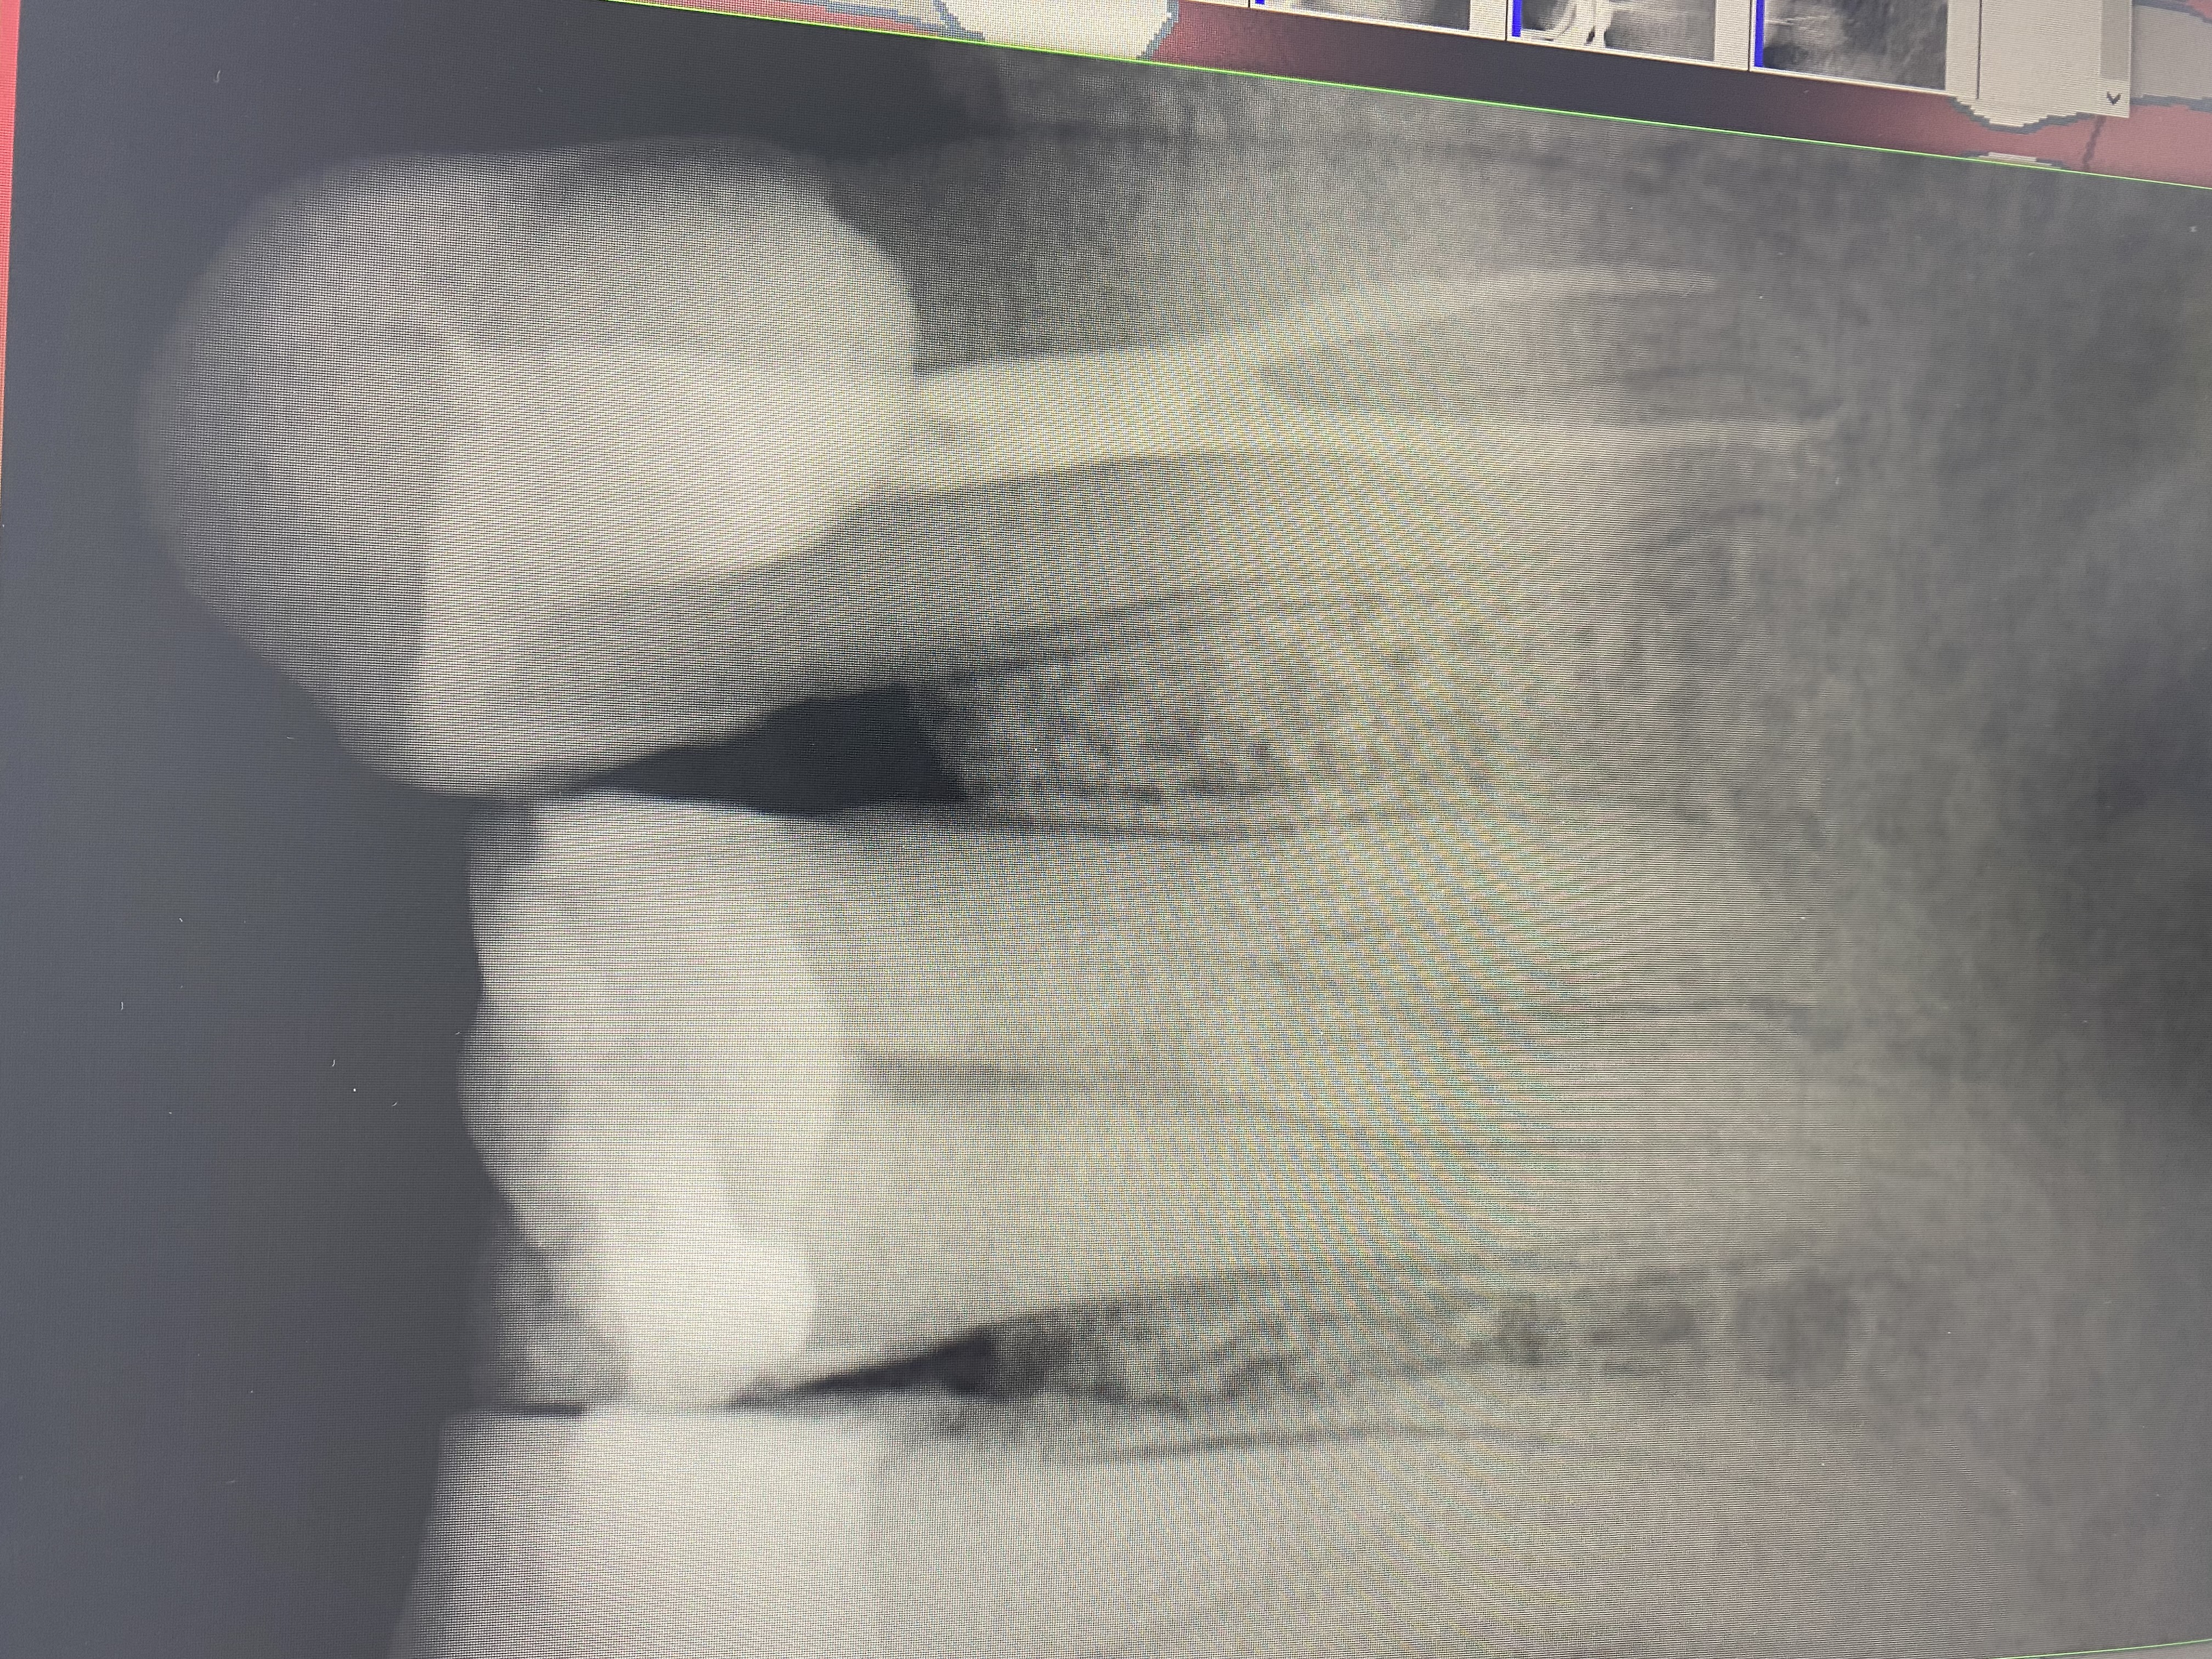

- Проведение полной профессиональной консультации по здоровью зубочелюстной системы, составление комплексного плана лечения, рекомендации по поддержанию качественной гигиены полости рта, обучение правильной технике чистки зубов, анализ снимков на визиографе и рентген-аппарате, анализ Клкт снимков

- Владение современными методиками пломбирования корневых каналов, обработки и распломбировки многокорневых зубов любой степени сложности